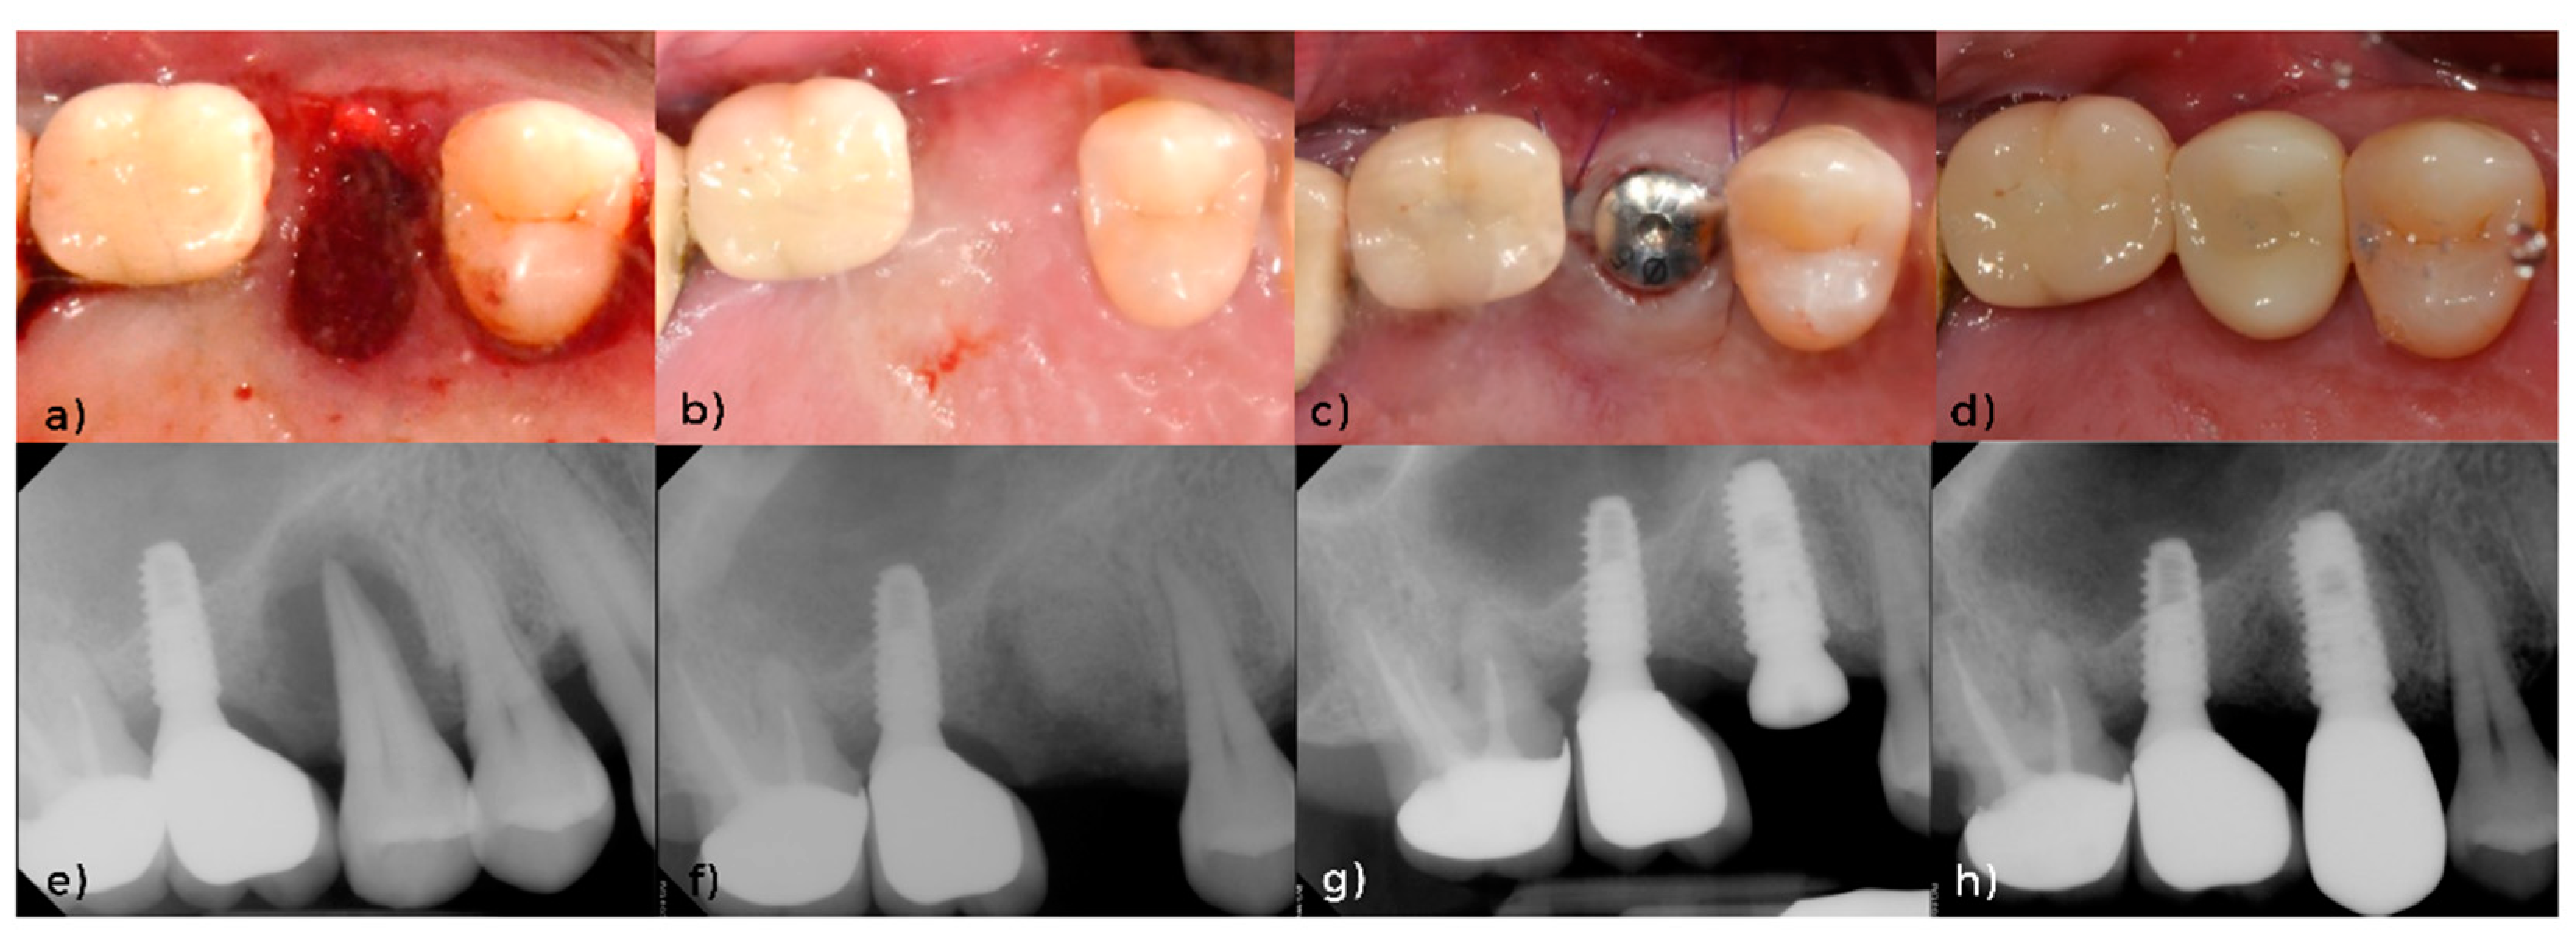

3.1. Clinical and Radiographical Evaluation